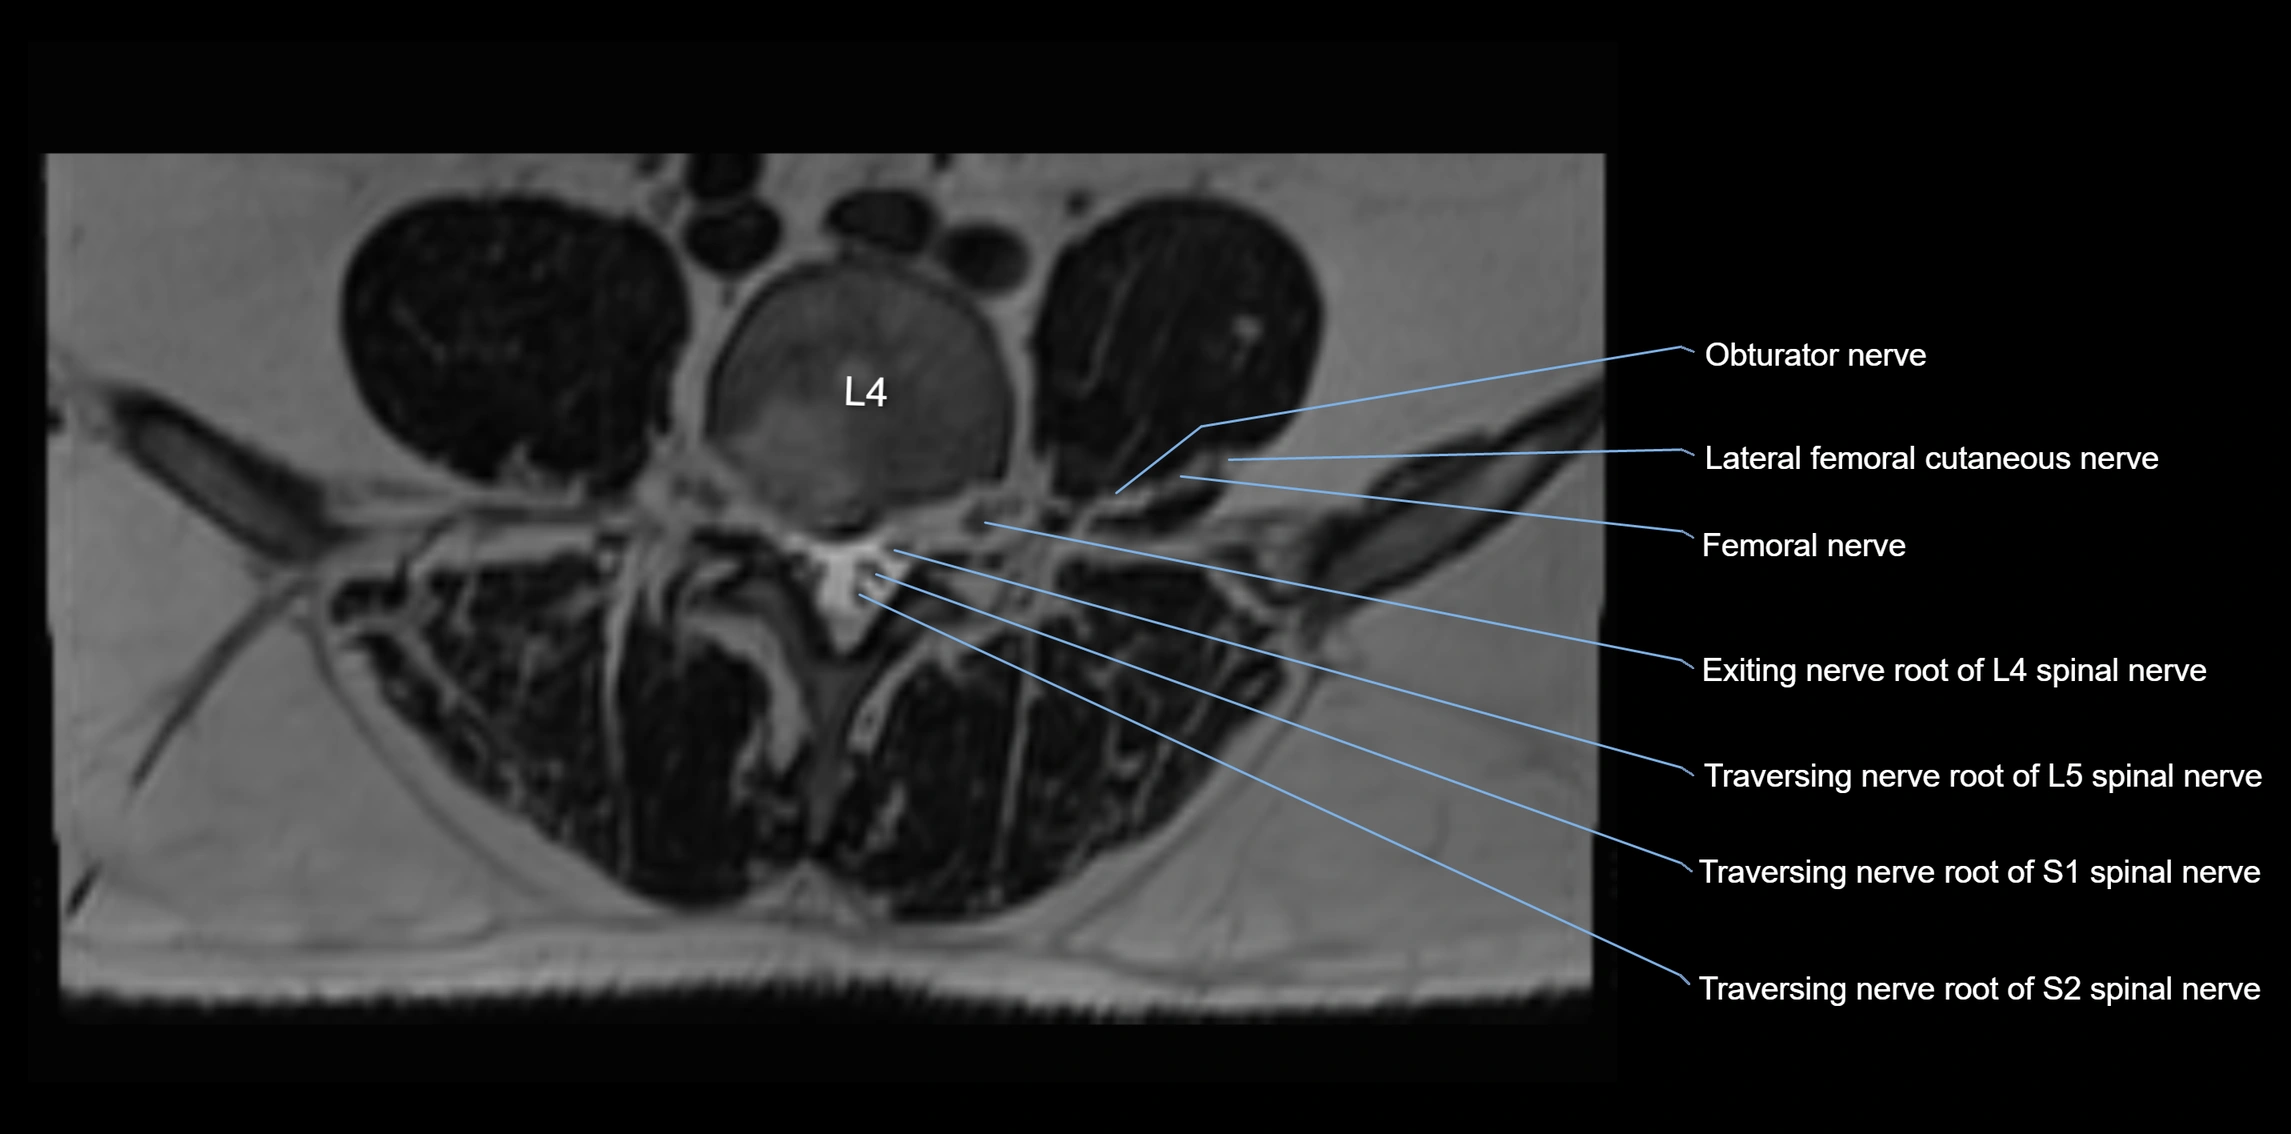

MRI image

image